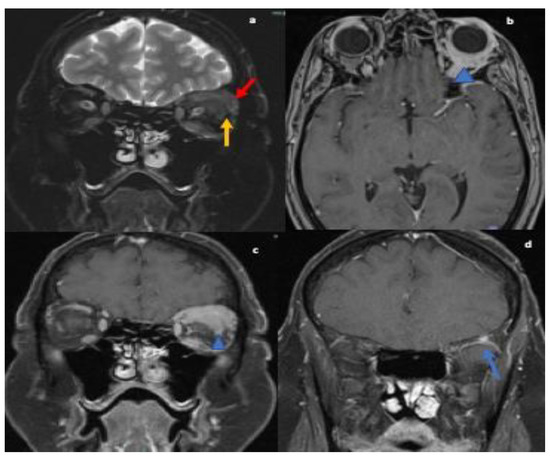

Figure 2.

MRI orbit T2 fat-suppressed coronal images reveals nodular thickening of the left lacrimal gland (red arrow; (a)), superior and lateral recti muscles (yellow arrow; (a)). T1-weighted post contrast axial (b) and coronal images (c) showing corresponding enhancement within muscles, lacrimal gland and in intraconal orbits surrounding the globe (blue arrowhead).T1 weighted post contrast coronal image (d) reveals enhancing nodule in the greater wing of left sphenoid concerning for osseous involvement (blue arrow).

The serum autoimmune and infectious work up were unremarkable. MRI orbits showed soft tissue thickening and enhancement in the left orbit with enlarged extraocular muscles, enlarged lacrimal gland and osseous involvement of the sphenoid bone (refer Figure 2). Differential at that time included cellulitis and lymphoproliferative disorder. She was started on oral antibiotics followed by left orbitotomy and excision of the mass. Biopsy of the mass revealed granulomas and the patient was diagnosed with orbital sarcoidosis. CT chest/abdomen/pelvis were without evidence of malignancy or systemic sarcoid. No lumbar puncture was performed as diagnosis was confirmed on biopsy.

She was started on oral prednisolone 10 mg daily, methotrexate 10 mg weekly; later increased to 15 mg weekly maintenance dosage. On her follow up visit, disease activity improved. The diplopia had resolved and the patient’s vision returned to baseline (20/20) bilaterally. She was continued on her medications with a reduction in methotrexate dose to 12.5 mg weekly and is being gradually tapered off of steroids (refer Table 1).

NS can affect the neurological system in various ways. One of these is cranial nerve involvement. Any of the cranial nerves can be involved in NS [11] but the most frequently reported is cranial nerve VII [1]. The first case in our series presented with lower motor neuron VII nerve palsy and VIII nerve involvement leading to a misdiagnosis of Bell’s palsy and ear infection. Multiple cranial nerve involvement, lesion within the brainstem and intramedullary lesions within the upper cervical spinal cord were seen on MRI were present in this case of NS. Despite treatment with steroids, the patient did not initially show improvement, complicating the case even further. The second case, initially diagnosed as orbital cellulitis, also demonstrated multiple cranial nerve involvement with ophthalmoplegia secondary to infiltration of the extraocular muscles due to granulomatous masses. The patient experienced loss of vision in the left eye due to surrounding inflammatory changes and mass effect. A subsequent biopsy confirmed the diagnosis of orbital sarcoidosis. Hence, cranial nerve involvement with other CNS lesions should raise suspicion for NS and treatment with steroids may not show a significant response initially.

The second case, initially diagnosed as orbital cellulitis, had second cranial nerve involvement with marked loss of vision in the left eye. There was also infiltration of extraocular muscles with pain upon eye movements and ophthalmoplegia due to granulomatous mass. Orbital sarcoid manifestations include thickening and enhancement of the intra-orbital and intracranial optic nerve and chiasm, optic atrophy and orbital masses. These are often mistaken as pseudotumor, glioma, meningioma of the optic nerve sheath, MS, or infectious etiology such as syphilis, lymphogranuloma venereum, leprosy, tularemia, torulosis, histoplasmosis, blastomycosis, and coccidioidomycosis [25,26,27,28,29]. Fast spin-echo fat suppressed axial and coronal T2, and T1 axial and coronal fat-suppressed contrast-enhanced MRI images are considered to be the standard protocol to investigate for intra-orbital or optic nerve disorders [30].